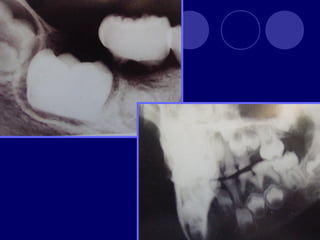

ODONTODISPLASIA REGIONAL

 Diente fantasma

 Dientes en forma de

concha, pequeños

con escasa raíz,

amplias cámaras

pulpares

 Rx: aspecto

fantasmagórico

• 72.

ODONTODISPLASIA REGIONAL  Dientefantasma  Dientes en forma de concha, pequeños con escasa raíz, amplias cámaras pulpares  Rx: aspecto fantasmagórico